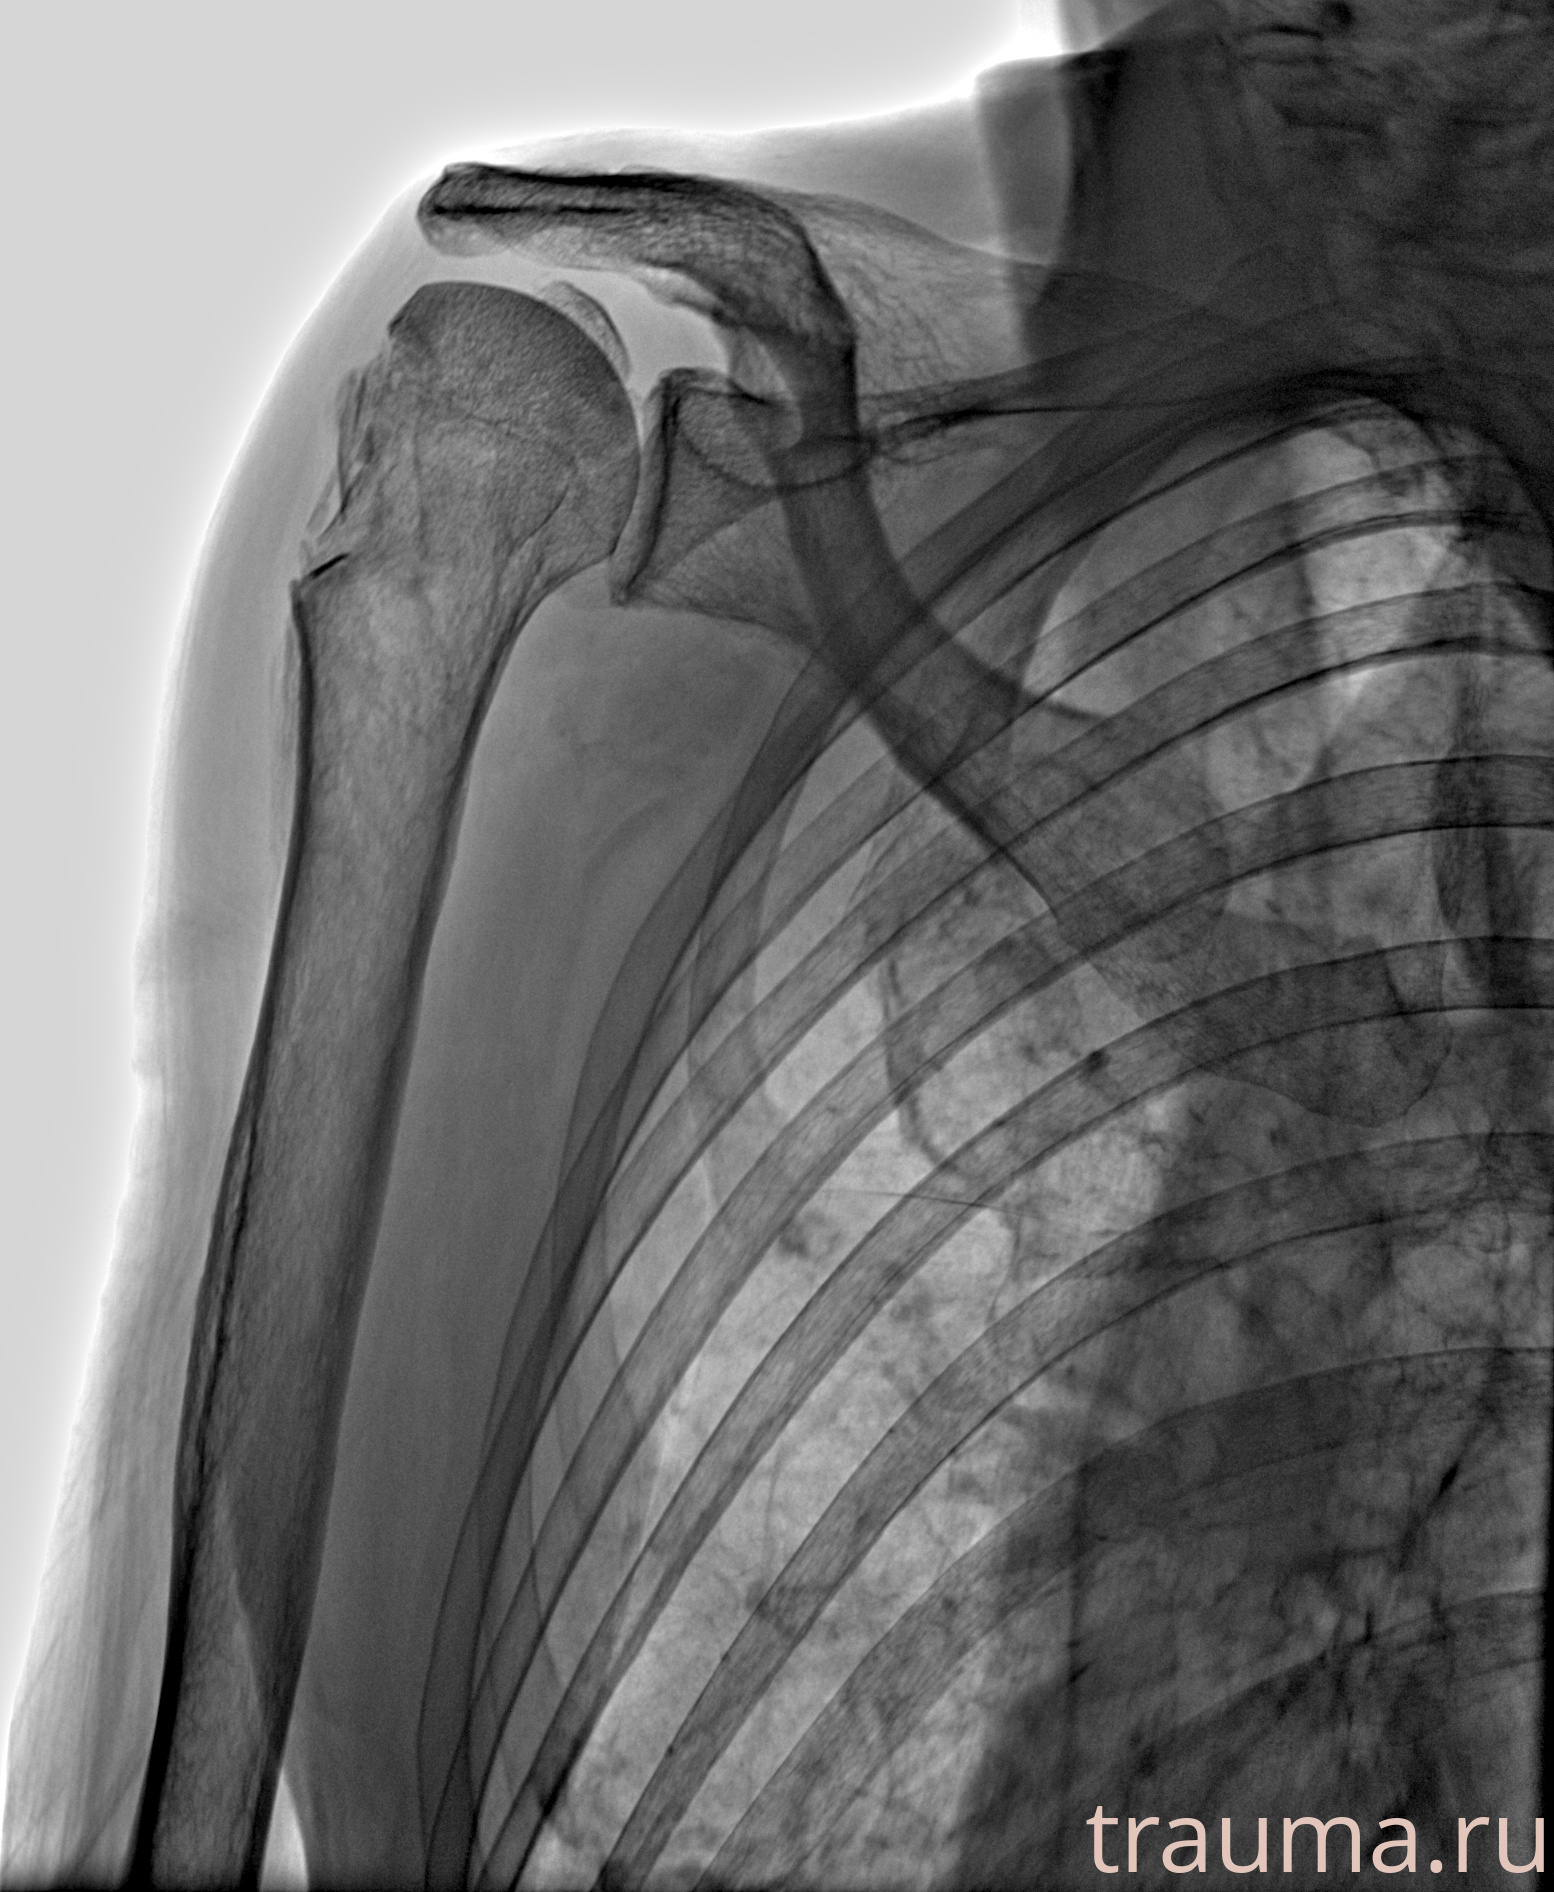

Рентгенограммы

Рентген на дому: по вашему адресу приезжает врач-рентгенолог, травматолог-ортопед с мобильным рентгеновским аппаратом, проводит диагностику травмы или заболевания, делает необходимые рентгенограммы, дает рекомендации по дальнейшему лечению. Получить качественные снимки в домашних условиях возможно благодаря уникальной методике, разработанной МосРентген Центром для института  Склифосовского

Яркость: 1   Контраст: 1   Инвертировать: 0 Увеличение: 1

Перетаскивайте мышь вверх/вниз для контраста, влево/право для яркости. Прокрутка колесом изменяет масштаб. Нажмите Сбросить для возврата к исходному изображению. При увеличении держите мышь в той области, которую хотите рассмотреть.